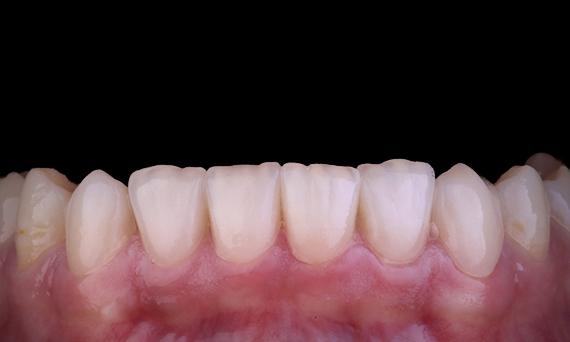

El paciente presentó pulpitis irreversible en la pieza dental 46. A partir de la radiografía preoperatoria, la pieza dental 46 se presenta con una raíz distal adicional (morfología dental Radix Entromolaris). Una escaneo CBCT ha confirmado la presencia de raíz distolingual con curvatura grave de la raíz. Una cuidadosa selección de limas es fundamental para esta raíz distobucal delicada.

Dr. Jack Lin, endodoncista, Sídney, NSW Australia